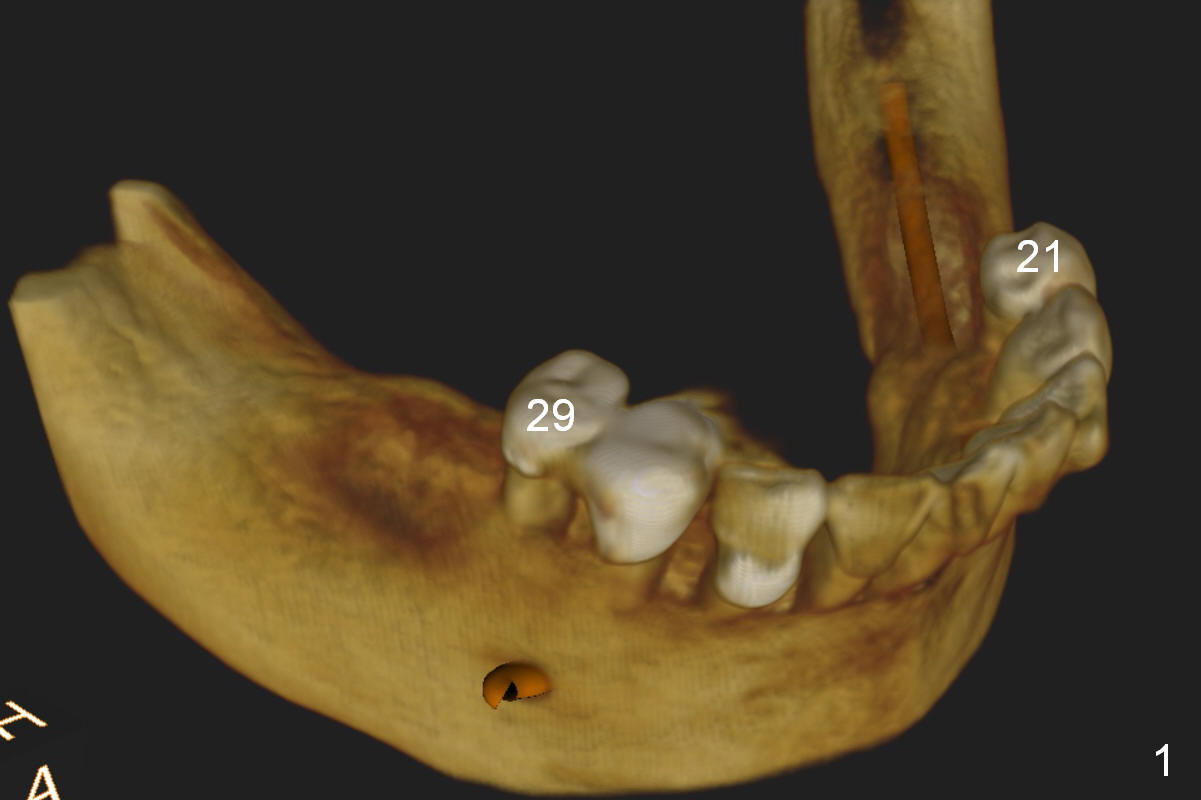

A 52-year-old lady has lost 5 lower posterior teeth (Fig.1 CBCT 3D image), which are restored by quadrant (LL).